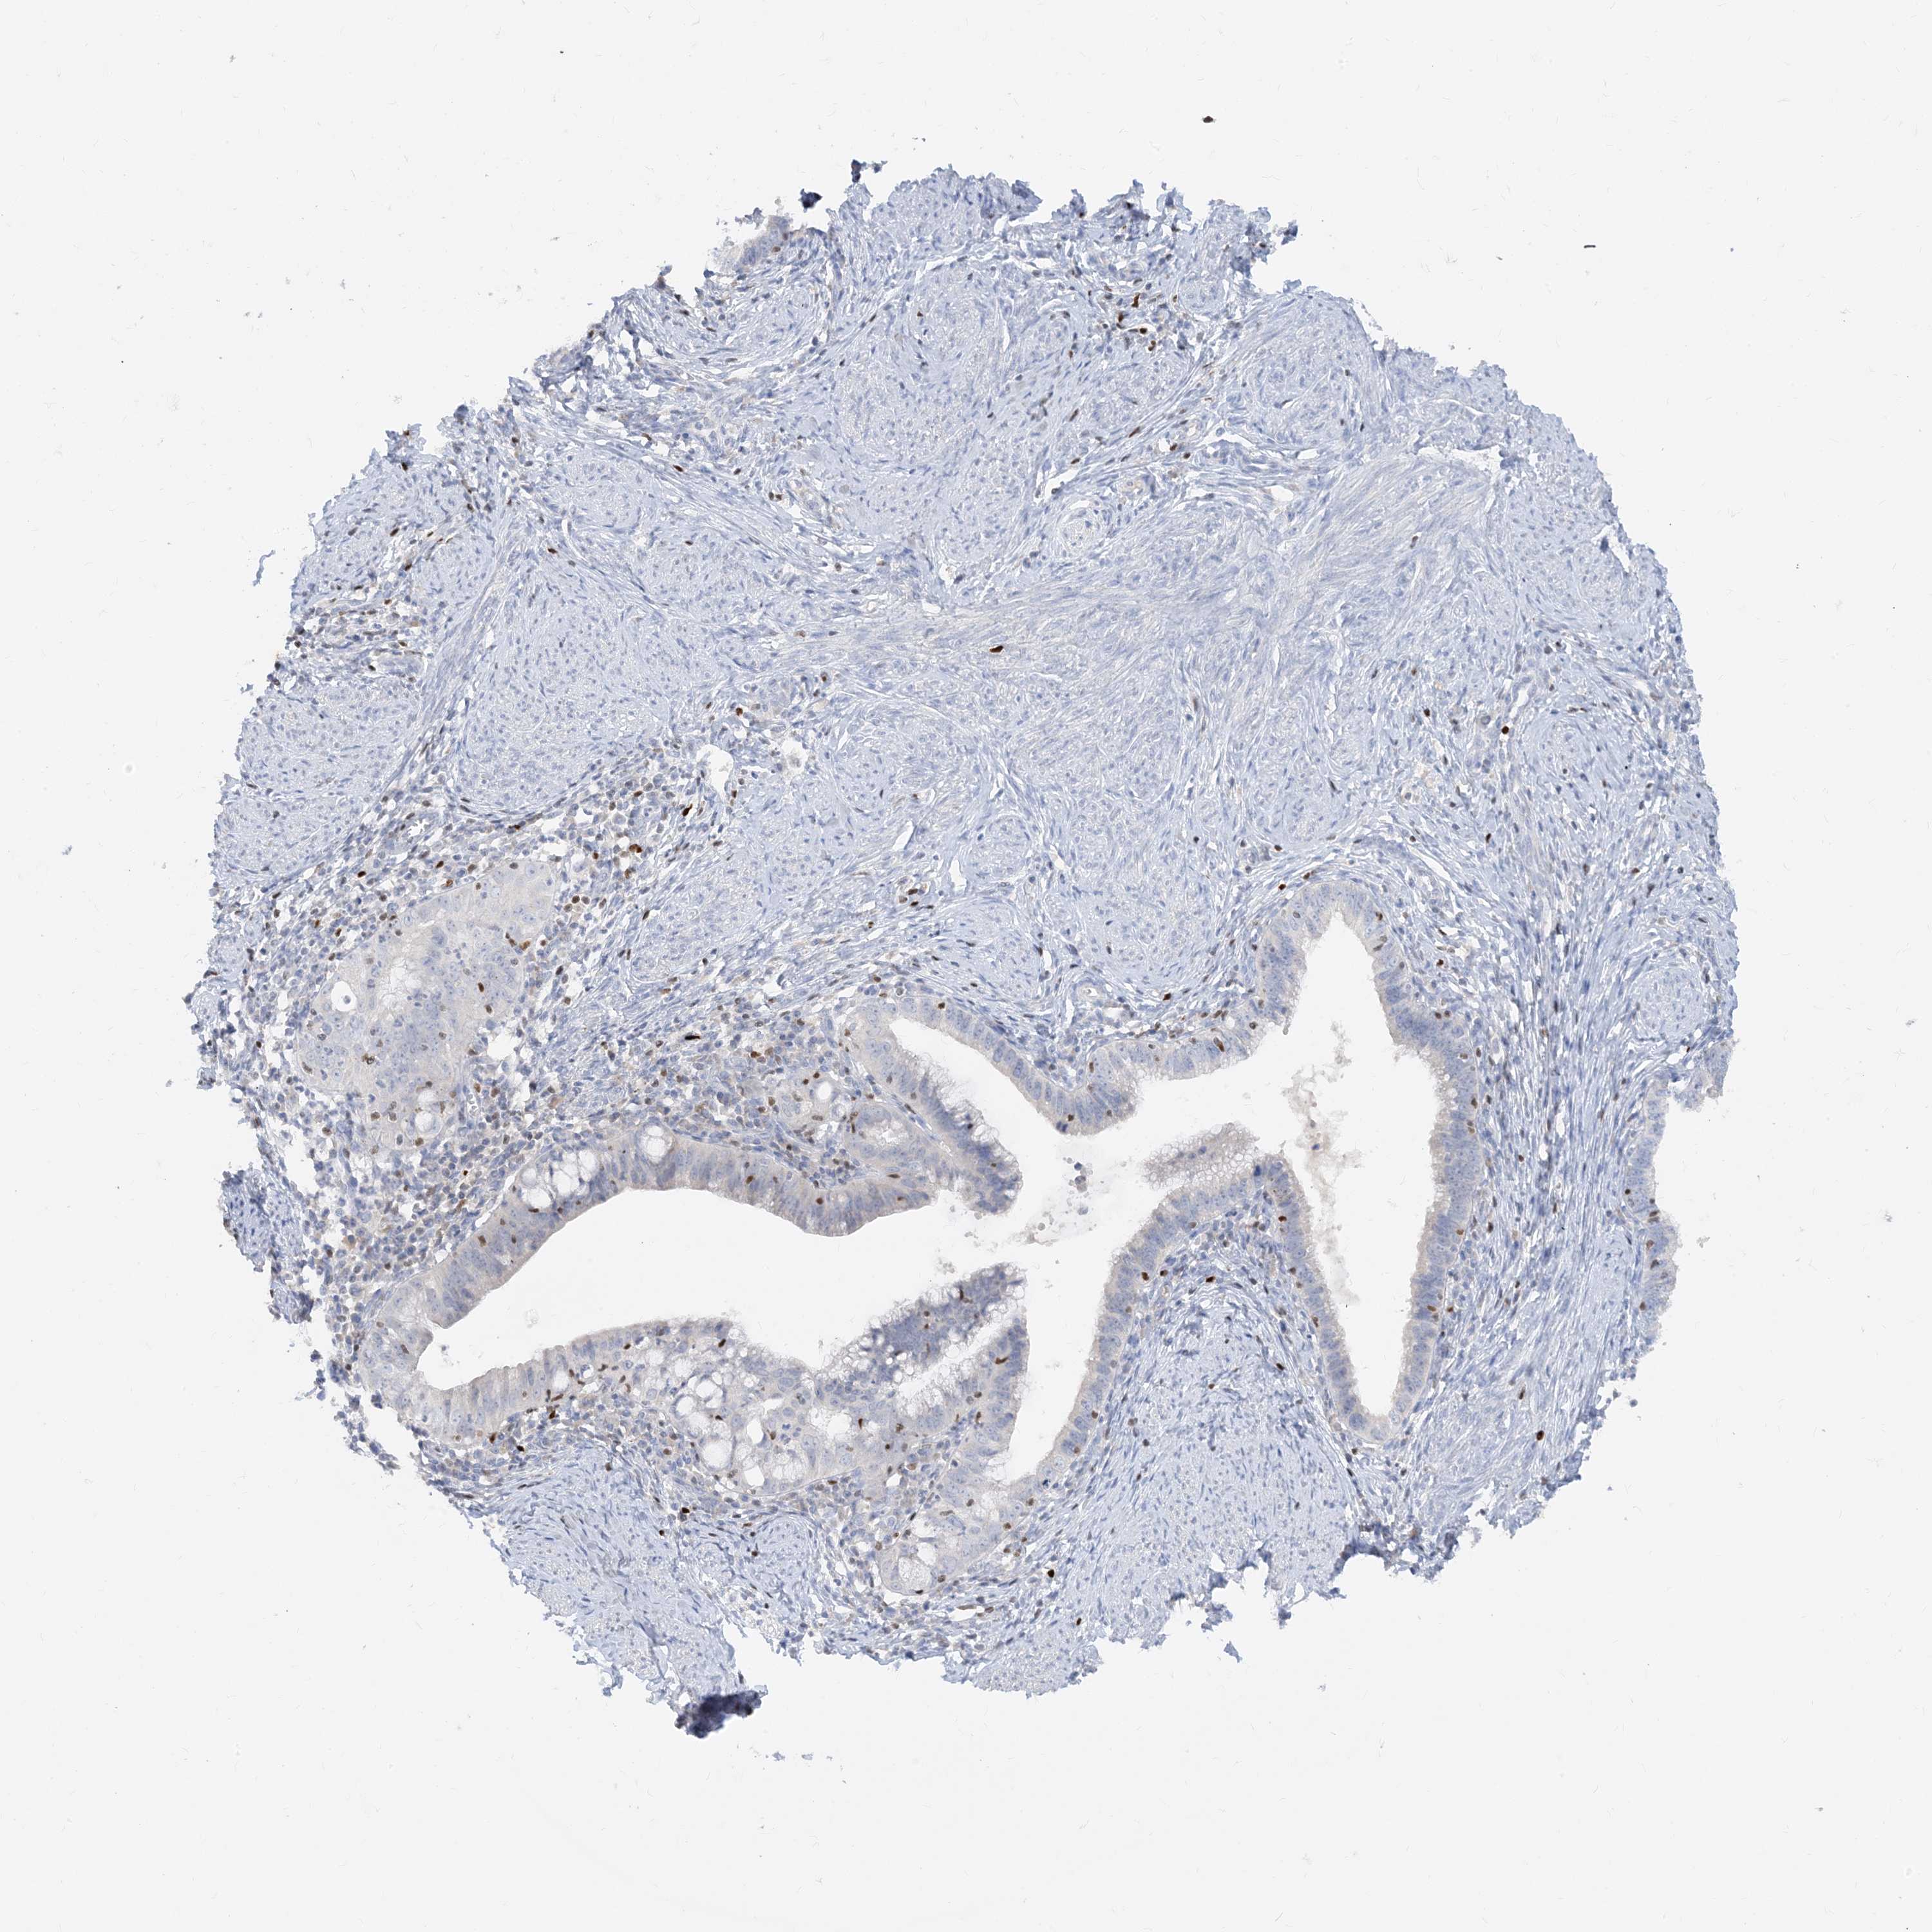

TBX21